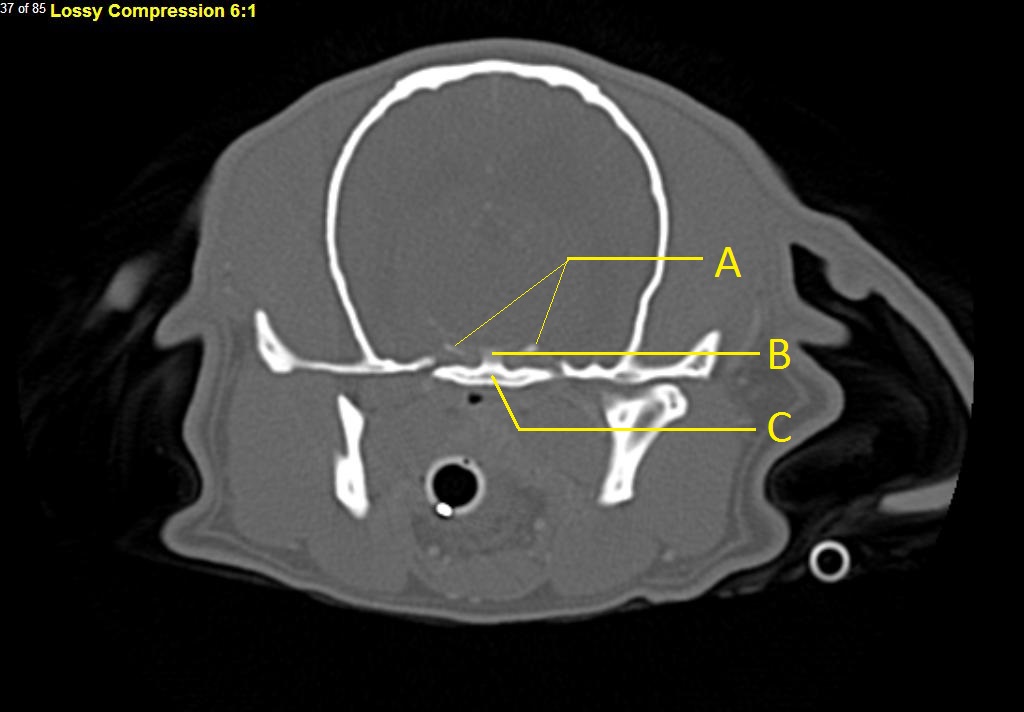

Q. Identify the structures labeled below:

A.

A. caudal clinoid process

B. dorsum sellae

C. basisphenoid bone